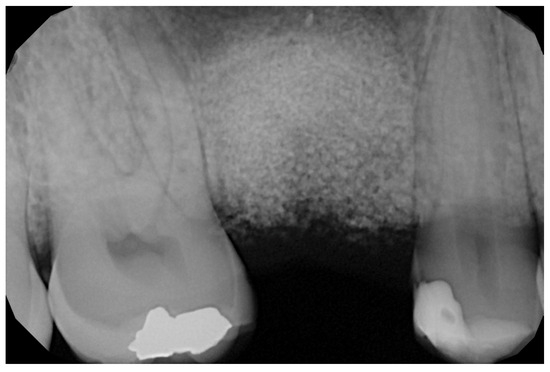

2.6. Case Presentation. Nano-HA Applied to Socket Preservation Procedures

3. Results